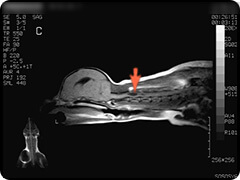

- 脊髄空洞症

- 脊髄内に空洞が生じた状態で、空洞内には脳脊髄液と同様の液体が満たされています。

疼痛がでたりふらつきや不全麻痺など症状は様々です。 -

頸部の脊髄です。水っぽいところが白く映っています。

水っぽいところは黒く映っています。